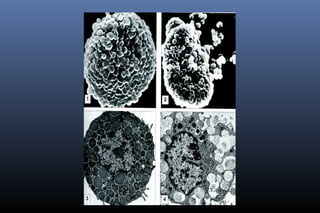

Macrófago

Macrófagos

 Célula grande com vacúolos citoplasmáticos

Macrófago + pseudopodes

macrófago interagindo com vários linfócitos